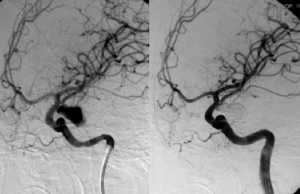

Στις παρακάτω εικόνες απεικονίζονται τα αποτελέσματα Εμβολισμού πραγματικών ανευρυσμάτων εγκεφάλου:

![]() |

Ανεύρυσμα έσω καρωτίδος πριν και μετά τον εμβολισμό |